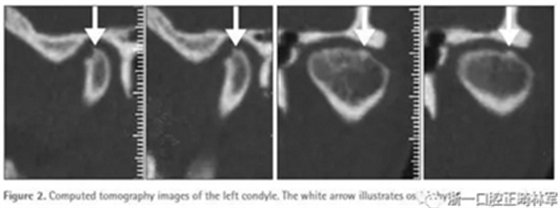

然而,患者的關(guān)節(jié)癥狀沒有改善甚至有惡化。并且,在左側(cè)髁突出現(xiàn)了骨刺樣退行性改變(Figure 2)。因此,進(jìn)行了視覺引導(dǎo)下的顳下頜關(guān)節(jié)沖洗和開放手術(shù),此后患者癥狀有改善。然而,雙側(cè)髁突的退行性變導(dǎo)致了開合和下頜順時針旋轉(zhuǎn)。對開合和髁突情況觀察一年以排除有害改變(Figure 1B)。而后,患者被介紹到正畸科糾正開合。